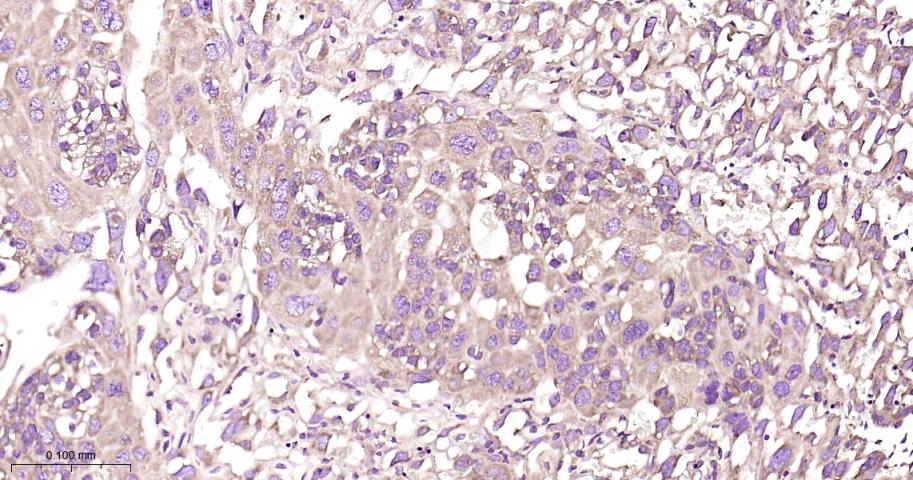

Paraformaldehyde-fixed, paraffin embedded Human Cervical Cancer; Antigen retrieval by boiling in sodium citrate buffer (pH6.0) for 15 min; Antibody incubation with RPS20 Monoclonal Antibody, Unconjugated(bsm-60503R) at 1:200 overnight at 4°C, followed by conjugation to the bs-0295G-HRP and DAB (C-0010) staining.